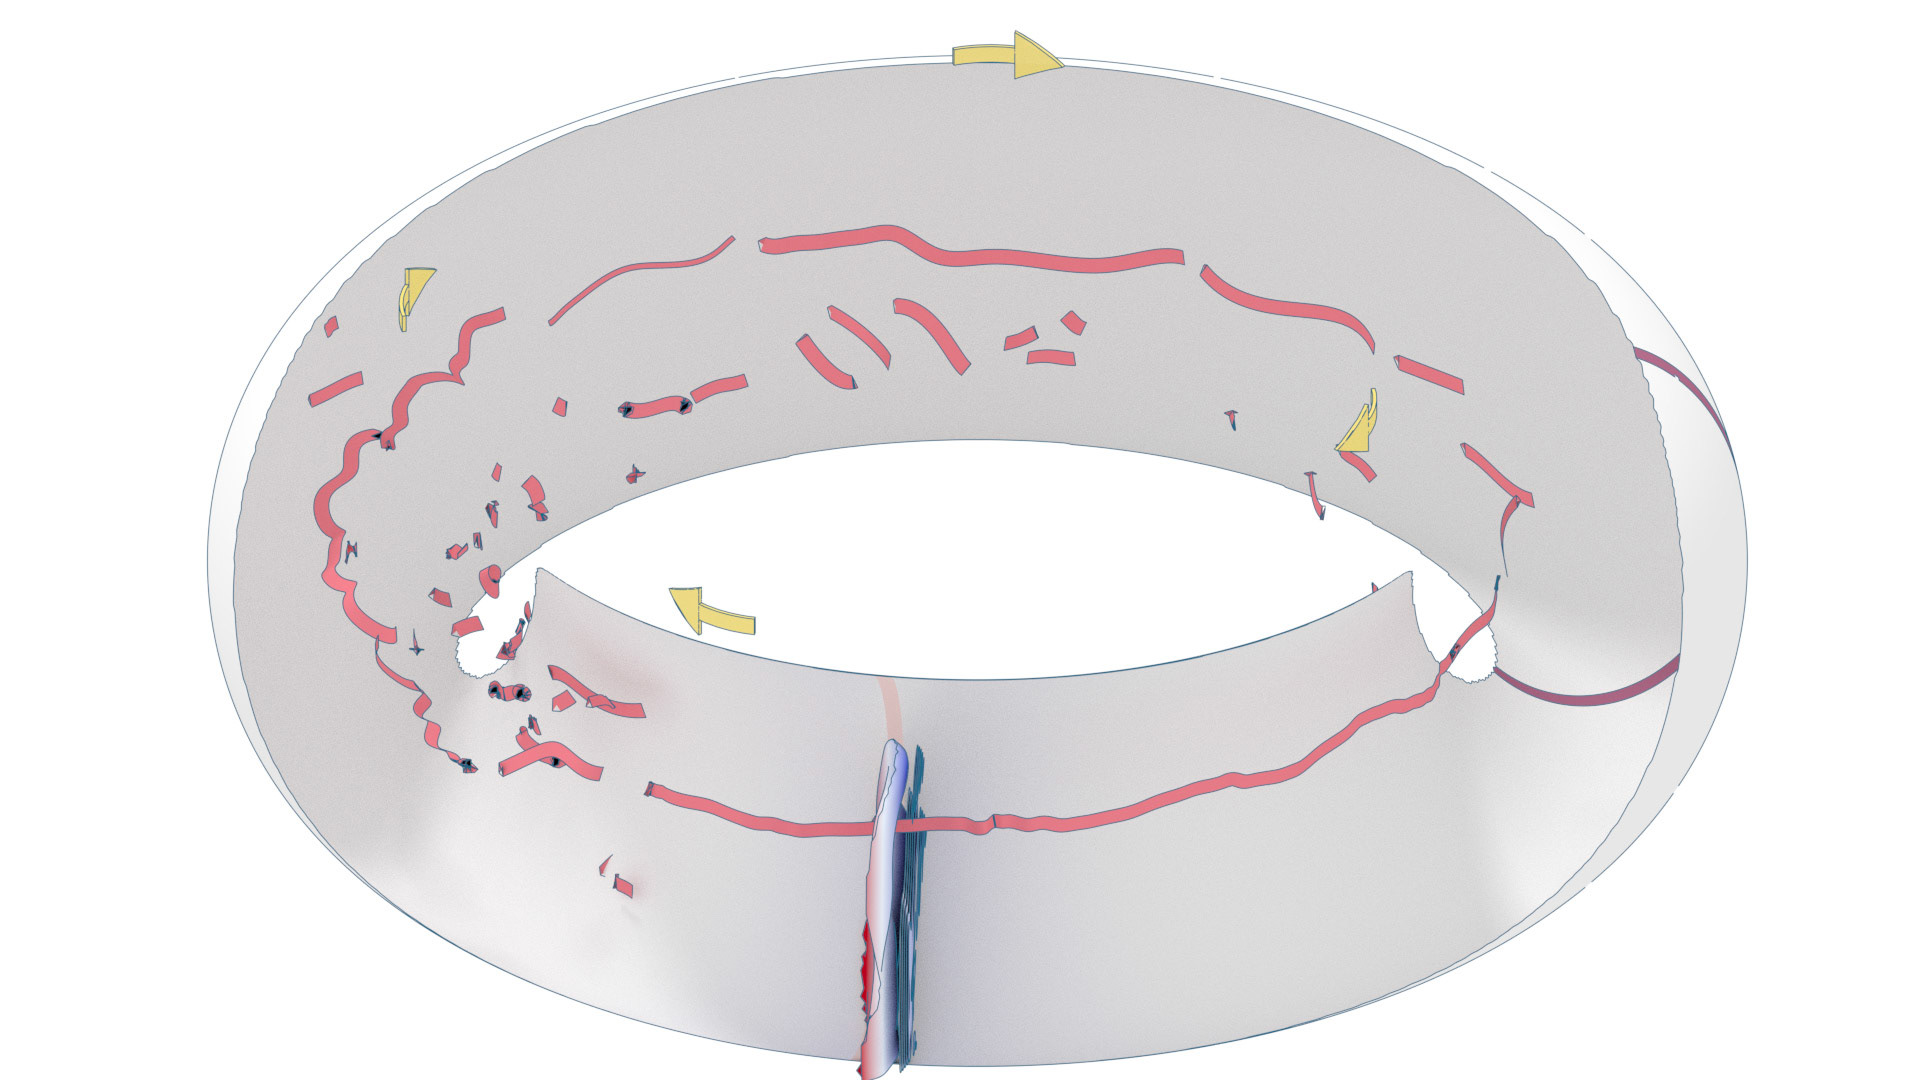

An ongoing collaboration with the Biomedical Simulation Lab (BSL), University of Toronto. In my role, I develop concept sketches and renderings that are then implemented algorithmically. The overall approach is to show turbulent flow visualizations without animation my mapping the transitions among states to carousel that corresponds to the cardiac cycle.